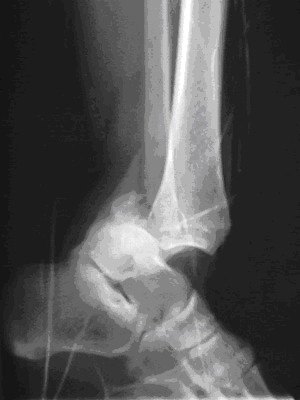

Der radiologische Befund des linken Sprunggelenks wird nun am Ende des November-Falls präsentiert

Die laut Röntgenbild verbliebene erhebliche Luxationfehlstellung hätte eigentlich nach dem beschriebenen 3. Repositionsmanöver auffallen müssen und hätte dann zu einem weiteren Repositionsversuch motiviert.

Auf dem Röntgenbild ist eine weitgehend erhaltene tibiale Gelenkfläche erkennbar (abgesehen von dem abgesprengten kleinen hinteren Volkmann-Dreieck mit sagittaler Länge von kleiner einem Viertel der tibialen Gelenkfläche ). Bei diesem Befund ist die Reluxation eines korrekt reponierten Sprunggelenks während des Transports wohl eher unwahrscheinlich.